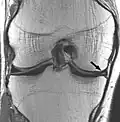

Proton density

Proton density-weighted image of a knee with synovial chondromatosis

Proton density (PD)- weighted images are created by having a long repetition time (TR) and a short echo time (TE).[36] On images of the brain, this sequence has a more pronounced distinction between grey matter (bright) and white matter (darker grey), but with little contrast between brain and CSF.[36] It is very useful for the detection of arthropathy and injury.[37]